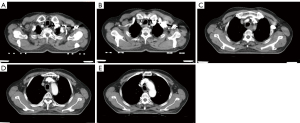

The CT scans of patients in the esophageal cancer group showed esophageal walls with irregular, needle-shaped, annular or localized eccentric thickening and narrowed lumens, which were dilated above the cancerous lesions. Some tumors compressed adjacent organs to deform and shift the organs, resulting in the disappearance of surrounding fat layers. Enhanced scans showed mild or moderate enhancement, with large diameter lesions unable to enhance central, low-density, necrotic areas. Among 53 patients with lymph node metastasis, 26 patients had lymph node metastasis of the right recurrent laryngeal nerve, which was consistent with the pathological report. The average short diameter of metastatic lymph nodes was (0.42±0.04) cm, and the average long diameter was (0.69±0.11) cm. Typical case images are shown in Figure 1A-E.